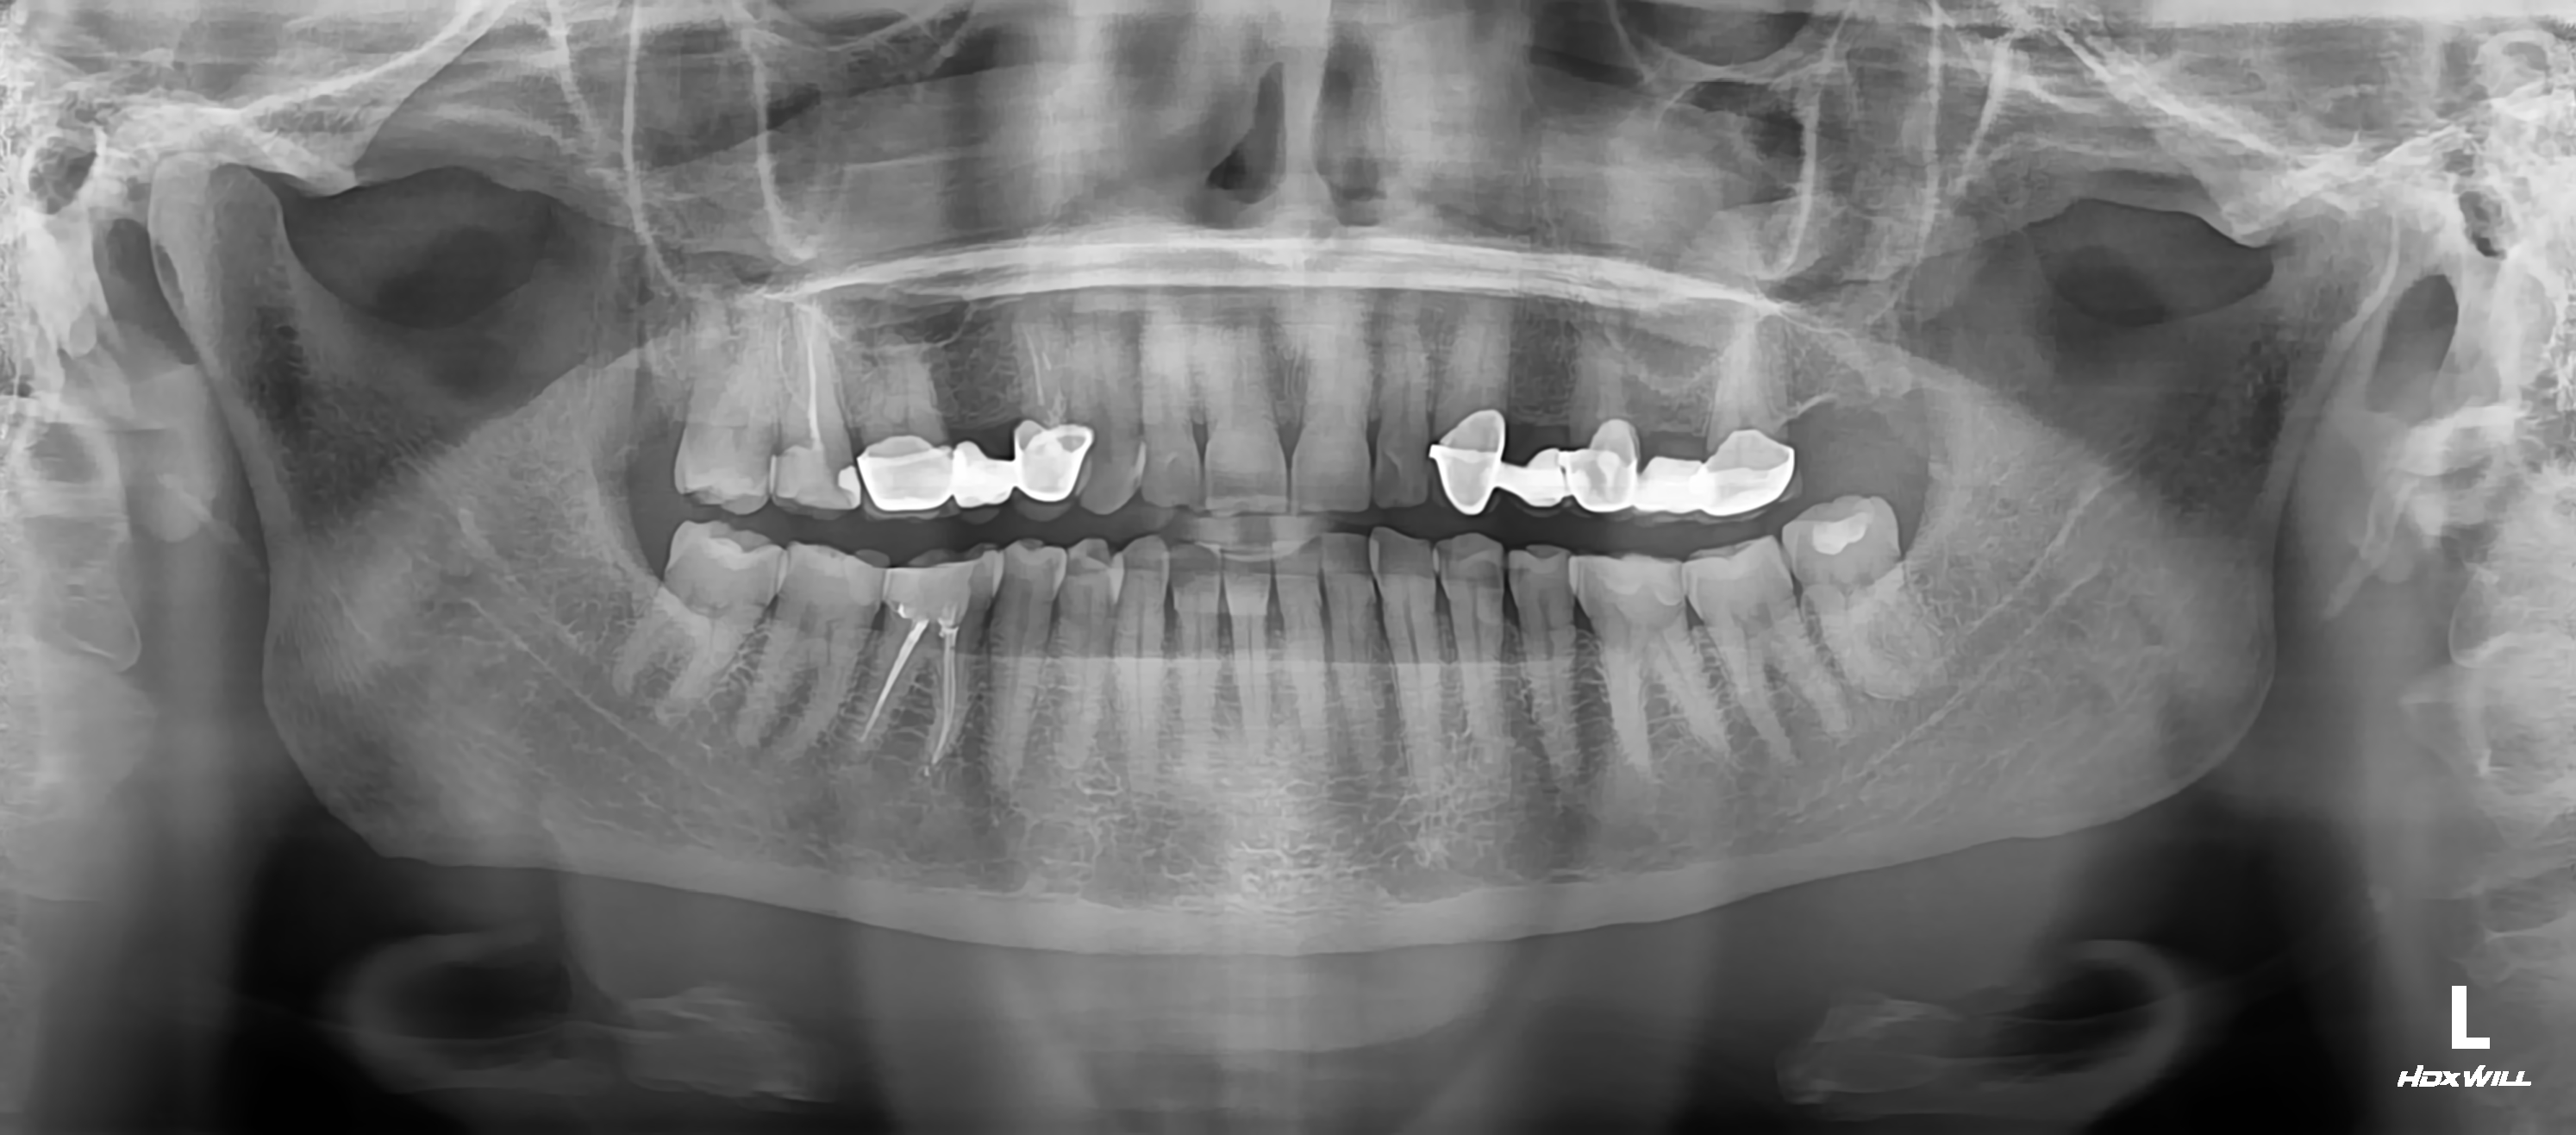

Технология протезирования зубов CEREC

Комплекс из технологии, оборудования и материалов для изготовления зубных микропротезов, шлифуемых из керамических блоков с применением специализированной.